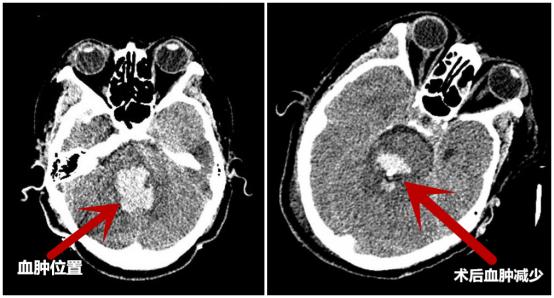

经术前充分准备,历时2小时,手术顺利完成。

术后复查CT,与术前CT对比血肿明显减少

术后,简国庆院长说道:机器人”辅助定位立体定向脑干血肿穿刺碎吸引流术,与传统手术相比,定位更精确,创伤小;并且通过术前精准的设计穿刺路径,能避开重要神经和血管,使患者能以最小的损伤取得最佳的治疗效果,使患者脑干的大血肿转化为小血肿,同时采用冲洗、药物溶血、引流等方式排空血肿,使患者获得生存机会,后期通过康复促醒提高患者生存质量。